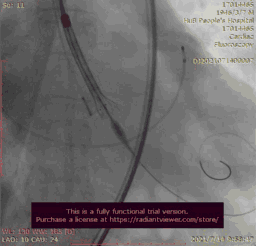

主动脉根部造影

输送器跨瓣